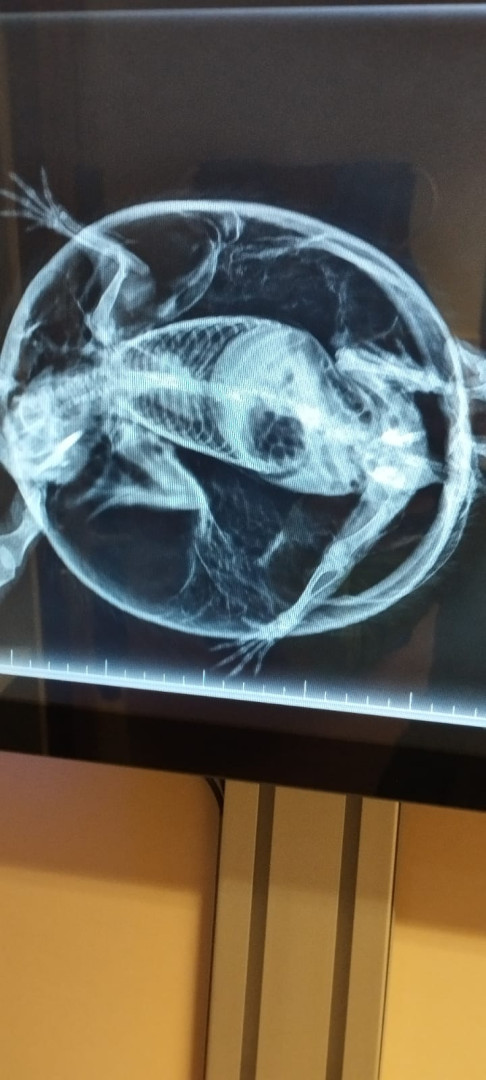

Ježek s balónovým syndromem doputoval do liberecké Archy. Veterináři ho vyfukovali dutou jehlou